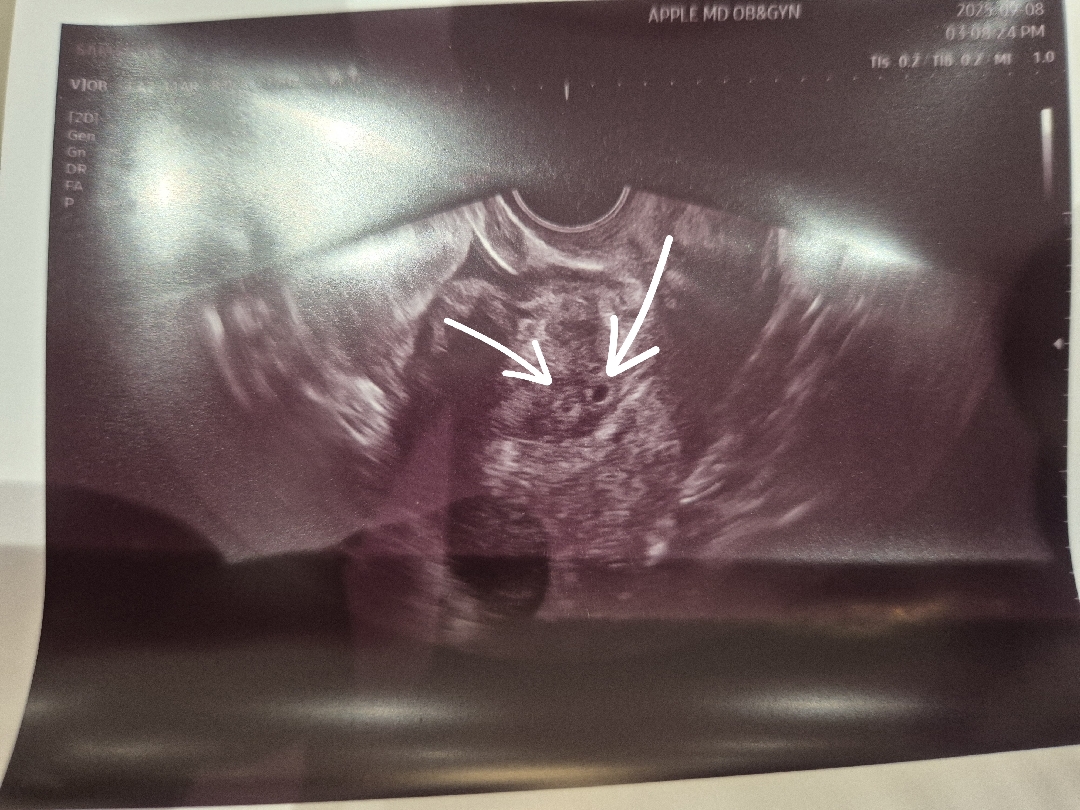

4주 2일차 아기집 보고왔어요!

배란 13일차 피검 254 배란 15일차 피검 500점대 배란 17일차 피검 2600점대... 어제 살짝피가비쳐서 병원갔더니 어머어마하게 피검수치올라가고, 벌써 아기집이 보이네요!! 원래 수요일 쯤볼수있을것 같았는데!! 우리쌍둥이 쑥과 마늘이♡